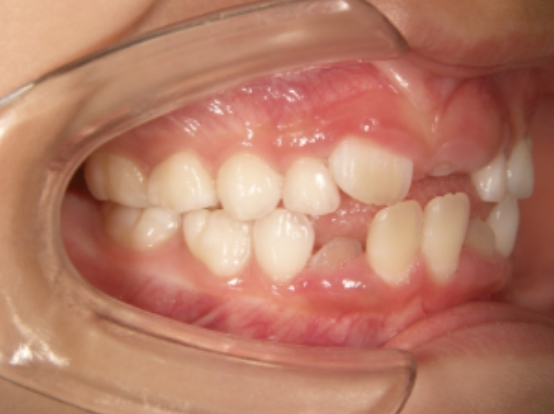

治療中➁ 小1:7y5m 装置使用後1か月で受け口が改善

治療中③ 小2:7y11m QH・BHで側方拡大、前歯の並べ替え

| カウンセリング・診断結果 | 前歯が受け口で生え変わってきているため、適正な成長へ誘導するために前歯の咬み合わせの改善が必要なことを説明したところ、診断を希望されたので精密検査へ進みました。 精密検査の結果、骨格的な反対咬合傾向はありますが、主に下顎前歯が突出している受け口です。 機能的に低位舌があり、下顎前歯が突出している原因の一つと考えられます。 口元は問題なくコンケーブも認められません。 |